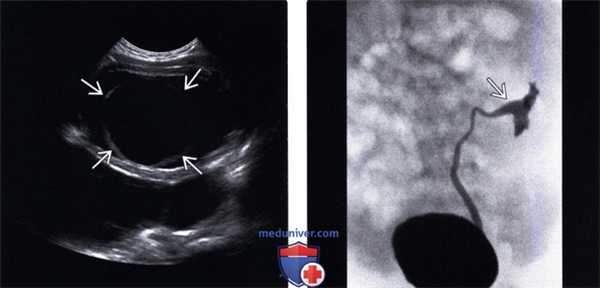

(Левый) На поперечном УЗ срезе визуализируется округлое тонкостенное анэхогенное образование в полости мочевого пузыря в сочетании с уретероцеле.

(Правый) На экстреторной цистоуретрограмме визуализируется симптом завянувшей лилии с контрастированием мочеточника и лоханки нижнего отдела почки и изменением нормальной оси вследствие обструкции верхней лоханки.